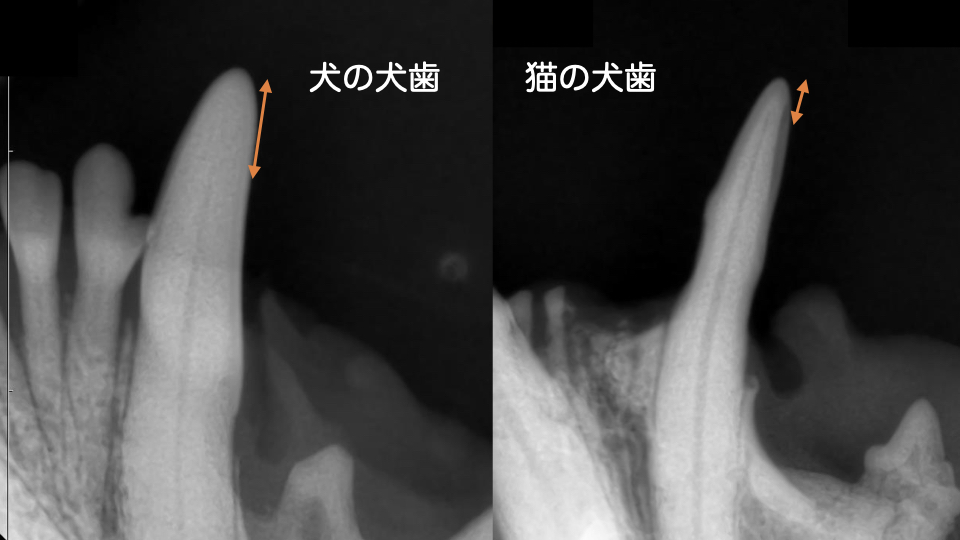

特に猫の犬歯は先端まで歯髄腔が通っているため、わずかに折れただけでも露髄が起こりやすい構造です。